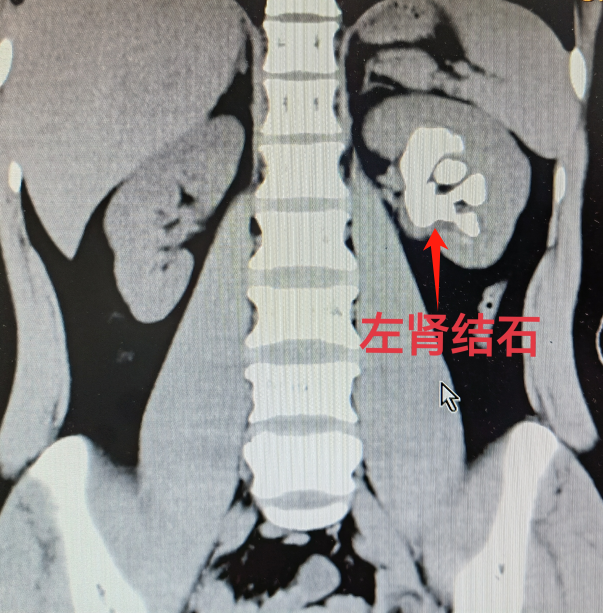

33岁的王女士,近两个月来因左侧腰痛并伴有活动后肉眼血尿而就医。经检查,被诊断为左肾完全性鹿角型肾结石,这种结石充满整个肾脏,直径达5厘米,且肾脏几乎没有积水,治疗难度较大。

术前左肾结石